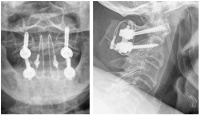

Abbildung 7: Röntgenaufnahmen im anterior-posterioren und seitlichen Strahlengang nach dorsaler Verschraubung von HWK 1 mit 2 durch Schrauben-Stab-System und Beckenkammspaninterposition mit Titan-Kabelcerclage gesichert.

Keywords: dorsale VerschraubungHWSRöntgenSchrauben-Stab-SystemTitan-Kabelcerclage